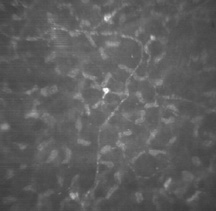

The corneal epithelium is the anterior-most cell layer of the cornea (Fig. 1). It is typically several cell layers thick, consisting of the apical cell squamous layer, the multilayered, polygonal-shaped wing cells beneath the apical layer, and the posterior-most layer of basal cells (Fig. 2). The wing cell layer is two or three cells thick in the central cornea, but tends to be four to five cells thick in the periphery. In total, the epithelium is approximately 50 μm thick in the central human cornea. The epithelium is in a constant state of turnover, with exfoliating apical cells being replaced by underlying wing cells. During normal exfoliation, desquamating cells are released only after the replacement cell has established new tight junctions with neighboring cells and the new apical membrane is capable of maintaining continuity of the tear film.9 Studies of induced exfoliation of a monolayer of epithelial cells with a biologic detergent indicate recovery of the paracellular barriers and transepithelial electric resistance in approximately 1 hour.10 The epithelium completely turns over in approximately 7 days.11 Once injured, a high degree of motility ensures coverage of a denuded area by adjacent basal cells, followed by replacement of the normal complement of cell layers. Basal cells are the only epithelial cells capable of mitosis; however, many epithelial cells originate as the progeny of limbal stem cells and migrate centripetally to supplement or replace cells lost through normal desquamation or injury.12–14 Using immunohistochemical staining for antibodies to keratins, Wiley and associates found regional heterogeneity indicating that the superior corneal periphery and limbus have the greatest numbers of stem cells producing replacement epithelial cells.15 Limbal stem cell deficiency may result in conjunctival epithelium invasion of the cornea, leading to vascularization, the appearance of goblet cells, and an irregular or unstable epithelium that reduces visual acuity and may produce pain or discomfort.16 The epithelium is known to chemically interact with keratocyte cells of the stroma. These interactions appear to be dominated by cytokines such as interleukin-1 (IL-1) and soluble Fas ligand that are released by injured epithelial cells. It would appear that IL-1 is a master regulator for corneal wound healing given its effect on keratocyte apoptosis and the modulation of matrix metalloproteinase and growth factors such as keratinocyte growth factor (KGF) and hepatocyte growth factor (HGF). The Fas ligand system is known to influence the immune privileged state of the cornea. In addition to the epithelial-to-keratocyte communication, keratocytes influence the state of the epithelium via HGF and KGF, which affect cell turnover, motility, and proliferation.17 APICAL CELLS Apical surface cells appear broad and flattened: 4 to 5 μm thick and 40 to 50 μm in diameter. Freshly emerged surface cells appear bright during specular microscopy and have relatively small numbers of microvilli covering their apical membrane (Fig. 3).18

The 300-nm thick glycocalyx (buffy cell coat) of the apical membrane can be preserved intact for histologic evaluation.7,8,19 The glycocalyx is composed of glycoprotein material, and numerous separate fine filaments become visible on the apical surface after tannic acid staining (Fig. 6). These filaments cover the tips and sides of the microplicae and microvilli extensively, inserting into the cell membrane. Angular bends and filament branching are evident, as well as a beaded substructure.19 The shortest filaments are 150 nm in length in the central cornea, while filaments 300 nm long are found on the conjunctival cell surfaces.19 The glycocalyx binds loosely with the overlying mucous layer and provides binding sites for immunoglobulin present in the tears.7 The margins of the apical cell membrane possess the important tight junctions surrounding the cell circumference near the apical margin.20 This junction complex is the correlate of the paracellular pathway of high resistance to ion flow. The lateral and basal membranes of the apical cells have gap junctions, numerous desmosomal junctions, and numerous membrane-bound vesicles. The cytoplasm contains a flattened nucleus (which probably disintegrates prior to desquamation), few organelles, and a notable increase in tonofilaments compared with the underlying cells. There are some aggregates of glycogen granules, small mitochondria, sparsely distributed free ribosomes, and poorly developed Golgi's complexes. Cytoplasmic vesicles are fairly numerous.21 WING CELLS Wing cells are distinguished by a variety of polygonal shapes and by their large ovoid nuclei. The cells are roughly 12 to 15 μm in diameter, and their cytoplasm contains few rough endoplasmic reticulum cisternae, mitochondria, or Golgi's complexes. The large numbers of cytoskeletal tonofilaments are approximately 8 nm in length, and numerous interdigitations exist along the cell membranes.21 Desmosomal and gap junctions are seen between adjacent wing cells and between basal and apical cells (Fig. 7). BASAL CELLS Basal cells appear as elongated polygonal cells approximately 10 μm in width and 15 to 20 μm in height, with prominent ovoid nuclei. The polygonal nature can be readily discerned in confocal microscopy images of the basal cell layer (Fig. 8). Buschke and associates22 showed that cell mitosis occurs in only 1 of 250 basal cells of the rat epithelium. In their study, mitosis occurred in irregular clumps of three to six cells, and mitotic cells were much more numerous in the periphery. The basal cell cytoplasm appears similar to that of the wing cells, as do the anterior and lateral cell membranes with their complement of desmosomal attachments. However, the basal membrane is notable for the presence of hemidesmosomes, which are discussed below. |